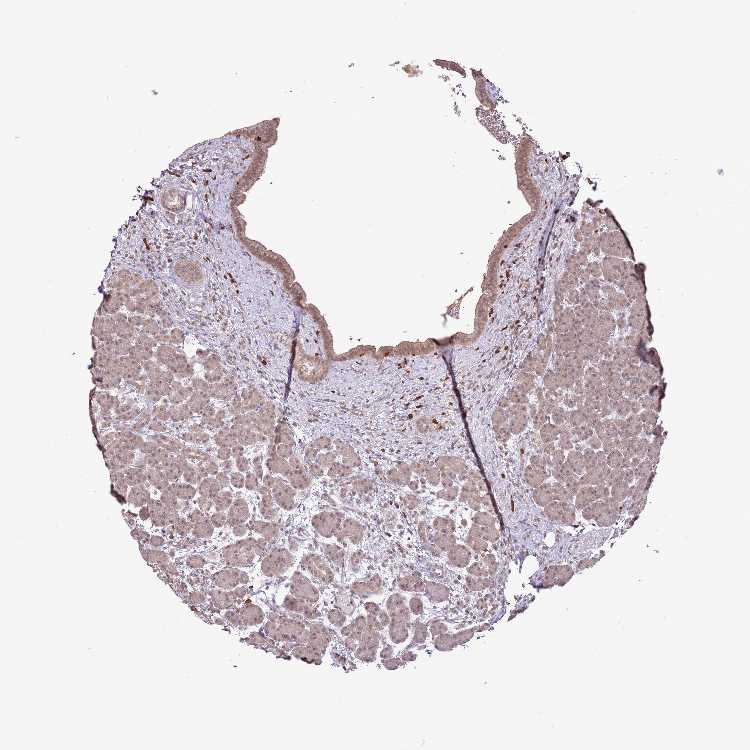

PANCREAS - Antibody stainingi

Antibody staining in the annotated cell types in the current human tissue is reported as not detected, low, medium, or high, based on conventional immunohistochemistry profiling in selected tissues. This score is based on the combination of the staining intensity and fraction of stained cells.

Each image is clickable and will lead to virtual microscopy that enables deeper exploration of all samples and also displays staining intensity scores, fraction scores and subcellular localization as well as patient and tissue information for each sample.

Antibody HPA046152

Exocrine glandular cells Low